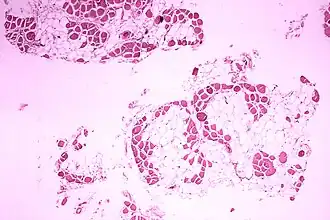

| Imagem microscópica do músculo da perna (gémeo) de um indivíduo com distrofia muscular de Duchenne. A secção transversal do tecido muscular mostra uma substituição extensa das fibras musculares por células adiposas. | |